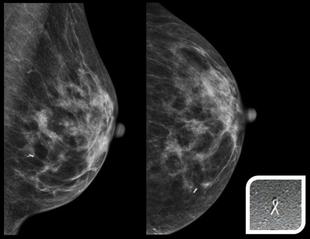

Meme ultrasonu veya mamografi ile saptanan derin yerleşimli ya da küçük boyutlu kanser açısından şüpheli özellikte olan kitlelerin cerrahi olarak çıkarılmasına yardımcı olmak için bu işlem yapılır. Ayrıca mamografide sadece patolojik (yani kanser açısından riskli olan mikrokalsifikasyon) kireçlenmeler görülen ancak henüz bir kitle oluşumuna yol açmayan çok çok erken dönemde kanser açısından şüpheli meme alanlarının çıkarılmasına da yardımcı olmak için de yapılır. Bu işlemde özel işaretleme telleri ya da coiller kullanılır. Görüntüleme eşliğinde bu teller olası kitlelerin hemen yanına konulur. Bu teller ucundaki çengel sayesinde dokuda sabit kalırlar ve yer değiştirmezler. Tel ile işaretlemeden sonra hasta operasyona gönderilir.